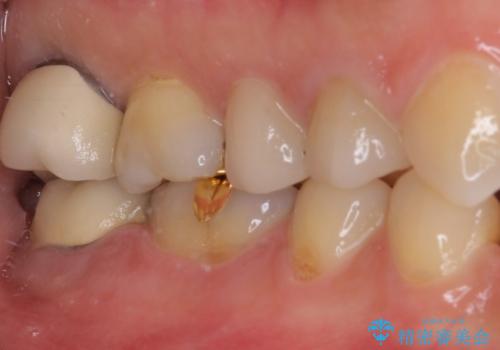

- 奥歯の間にものが挟まって不快であるとのことで来院された患者様です。

検査を行った結果、非常に強い咬合力により隣の歯との隣接面にひびが入り、虫歯が拡大している状態でした。

部分的にゴールドインレーが装着されていたので、虫歯と合わせて除去し、新たにゴールドインレーにて修復治療を行うこととしました。